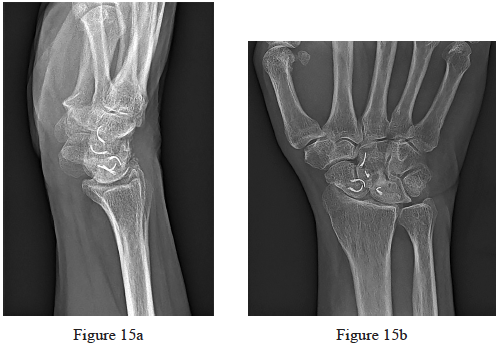

15. Figures 15a and 15b are the radiographs of a 62-year-old right-hand-dominant woman who has right wrist pain. Thirty years ago she underwent scapholunate ligament repair. She never fully regained wrist motion or strength and reports that her pain and stiffness have progressed substantially during the last 5 years. An examination reveals decreased wrist flexion and extension and tenderness along the radiocarpal joint. She attempted bracing and corticosteroid injections without experiencing lasting symptom relief. Which surgical treatment will most likely provide pain relief and preserve motion?